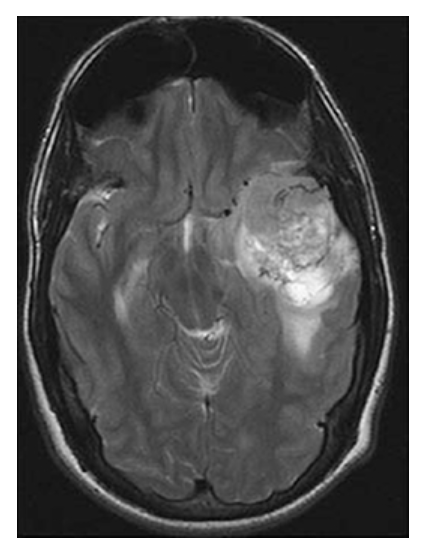

Astrocytoma. Axial T2W image shows the left temporal mass with surrounding high-signal edema.